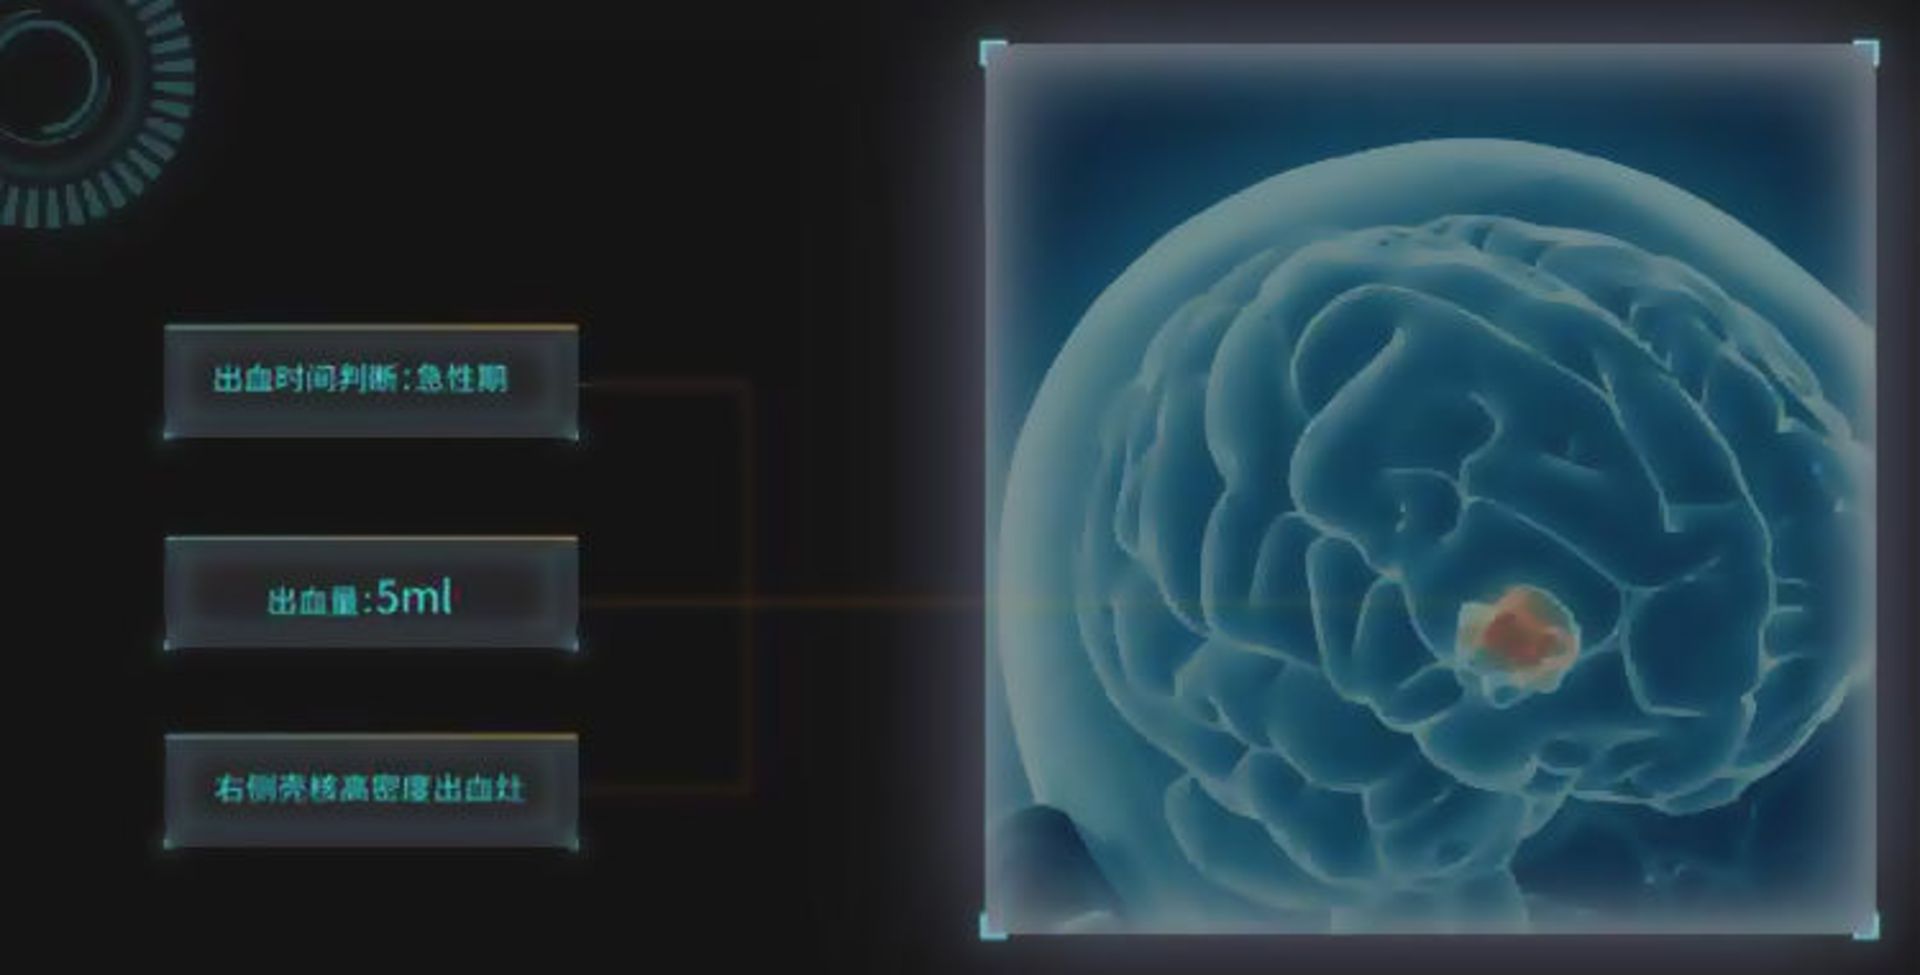

کمبود پزشک در چین بدین معنی است که جمعیت کنونی پزشکان با فشار کاری فزایندهای برای رسیدگی به وضعیت سلامتی بیماران روبهرو هستند؛ معضلی که اغلب منجر به تشخیصهای اشتباه میشود. همین مسئله مهندسان را بر آن داشته تا در اندیشهی استفاده از یادگیری عمیق و هوش مصنوعی برای تحلیل تصاویر پزشکی باشند. بنابر پیشبینیهای محققان IDC، ارزش بازار تشخیصهای پزشکی با هوش مصنوعی در چین، در سال ۲۰۱۷ از مرز ۲۷ میلیون دلار گذشته است و تا سال ۲۰۲۲ از مرز ۸۷۰ میلیون دلار هم عبور خواهد کرد.

یکی از بازیگران نوپا در این بازار، شرکتی موسوم به 12Sigma در سندیهگو است که توسط دو مهندس سابق کوالکام تأسیس شده و اکنون دارای تیمهای تحقیقاتی در چین است. این شرکت، درکنار برخی رقبای چینی نظیر Yitu، Infervision و تعداد دیگری از شرکتها به کمک پزشکان میآیند تا در آزمایشها و تصاویر پزشکی، سلولهای سرطانی را شناسایی کنند. مابین ماههای ژانویه تا مه سال گذشته، برخی از شرکتهای چینی فعال در این حوزه توانستهاند سرمایهای بالغ بر ۱۰ میلیون یوآن (۱.۴۸ میلیون دلار) را بهدست آورند. مجموعهی 12Sigma هم بهتنهایی توانسته در دور دوم جمعآوری سرمایه، مبلغی در حدود ۲۰۰ میلیون یوآن (۲۹.۶ میلیون دلار) را به دست آورد. علاوهبر این، 12Sigma مصمم است تا با جمعآوری سرمایهی بیشتر، تیم فروش خود را گسترش داده و محصولات جدیدی را توسعه دهد.

در اغلب صنایع، ممکن است هوش مصنوعی در دسترس باشد؛ اما هیچ مشکل حیاتی برای حل کردن وجود ندارد. در آن حوزهها شما در حال ایجاد نوعی تقاضای جدید هستید. اما در حوزهی سلامت یک مشکل واضح وجود دارد. در این حوزه با این نیاز سر و کار داریم که چگونه بهنحوی کارآمد بیماریها را تنها با دیدن یک تصویر پزشکی شناسایی کنیم.